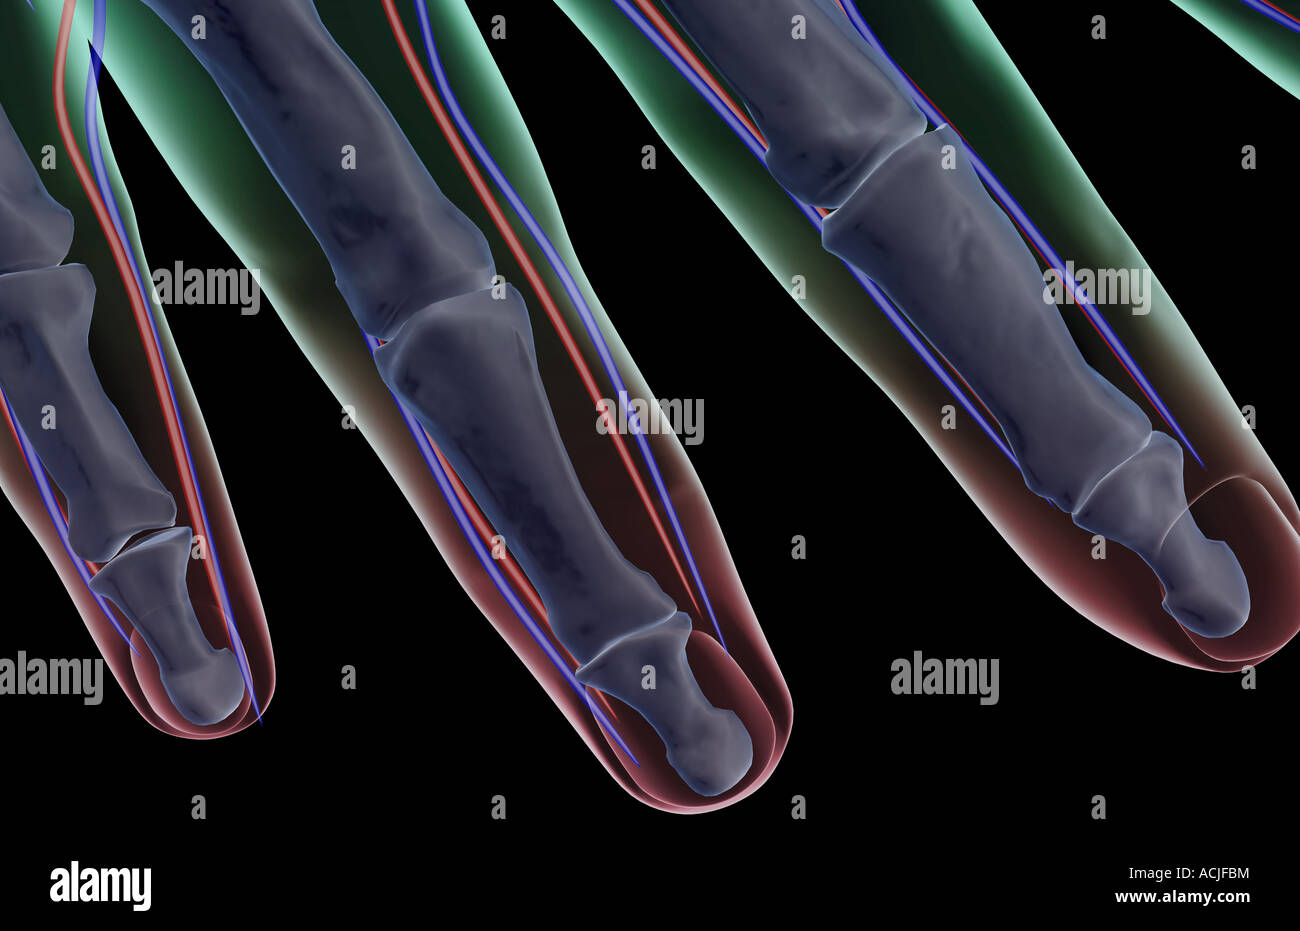

The blood supply of the fingers Stock Photohttps://www.alamy.com/image-license-details/?v=1https://www.alamy.com/stock-photo-the-blood-supply-of-the-fingers-13170103.html

The blood supply of the fingers Stock Photohttps://www.alamy.com/image-license-details/?v=1https://www.alamy.com/stock-photo-the-blood-supply-of-the-fingers-13170103.htmlRFACJFBM–The blood supply of the fingers